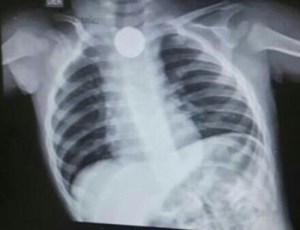

Llegamos al hospital, al pasar de las horas le tomaron una placa y verificaron que había un objeto en la parte de su tráquea pero que le permitía respirar normalmente.

Inicialmente creíamos que era una moneda (En ese hospital le dieron acetaminofén y metoclopramida para que no vomitara y eso le sulfato mas rápido la batería). Al pasar de las horas en el hospital donde entramos inicialmente, por no contar con los recursos suficientes no pudieron hacer nada y logramos llevarlo hasta Medellín; ya Martín llevaba alrededor de 20 horas con la batería en su tráquea haciéndole los daños respectivos.

Inmediatamente llegamos, miraron los RX y dijeron que no daba espera, en el momento no había endoscopista pediátrico por lo que un endoscopista para adulto a quien hoy digo que fue un mago, luego de 4 largas horas pudo lograr sacarle la batería que ya había causado una quemadura del 80% de su esófago del tamaño de un pitillo. En ese momento una angustia me mataba porque jamás debí permitir tener tantas cosas «NO APTAS PARA SU EDAD» a su alcance.